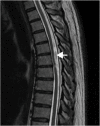

Spinal arachnoid cysts: A case series & systematic review of the literature

Introduction: Spinal arachnoid cysts (SACs) are rare lesions with challenging and controversial management.

Results: Our series consisted of 11 patients, M:F 8:3, mean age 47.8 years (range 18-73 years). Mean follow-up was 19 months (range 5-36 months). SACs were excised or marsupialised (7), fenestrated (3) or partially excised (1). Eight patients had expansile duroplasty, 3 primary dural closure. One patient had a cystoperitoneal shunt. All patients were AIS D preoperatively; 4 remained unchanged and 7 improved to AIS E at follow-up. Our systematic search retrieved 725 citations. Fourteen case series met the inclusion criteria. There was no evidence to support superiority of one surgical strategy over another. Surgery for symptomatic patients resulted in positive clinical outcomes.

Discussion and conclusions: Symptomatic SACs require surgical intervention. Limited evidence suggests that decompressing the cord, breakdown of arachnoid adhesions, and establishing CSF flow by consideration of expansile duroplasty are important for positive outcomes.